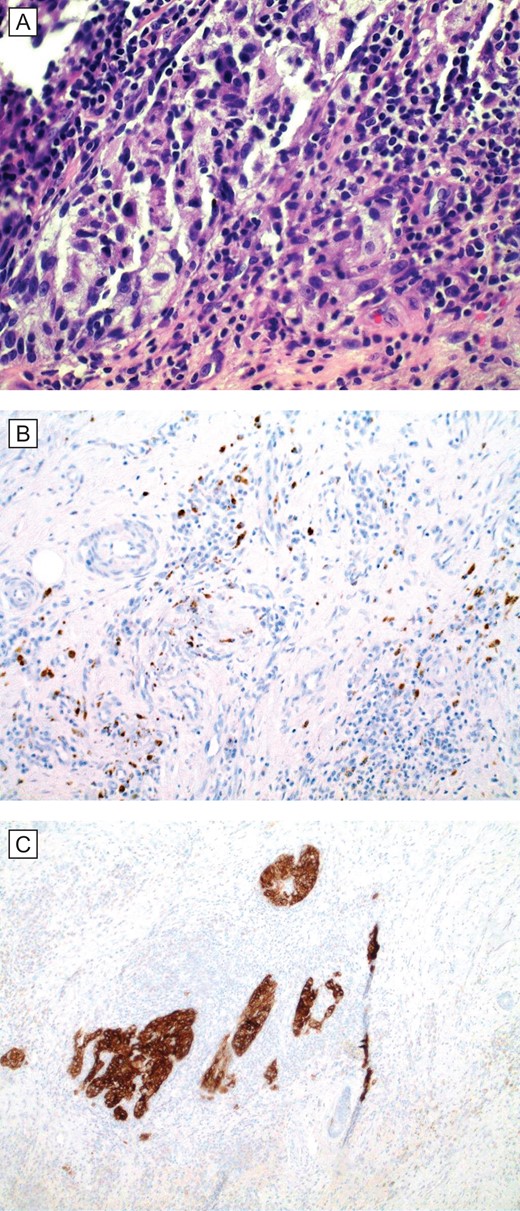

(A) Histopathologic examination (H&E; original magnification: 400×) shows small foci of residual and scant melanoma cells. (B and C), special stains (IHC; original magnification: 400×) MART1/MelanA and HMB45, respectively, are cytoplasmic stains that highlight the presence of scattered melanoma cells in the dermis.